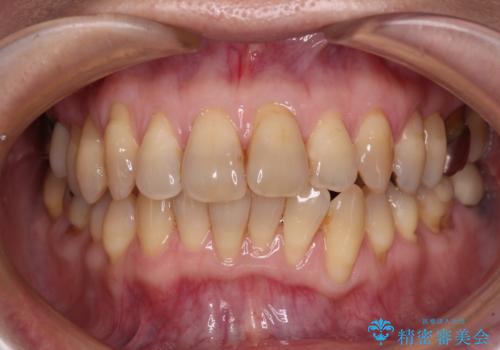

- 上下前歯のデコボコと、奥歯の銀歯を気にして来院された患者様です。

仕事柄あまり目立つ装置は付けることは避けたいとのことで、インビザラインによるマウスピース矯正を行うこととしました。

概ね歯列が整ったところで銀歯の全てをセラミッククラウンなどに置き換え、その後インビザラインを1セット使用して仕上げていくこととしました。